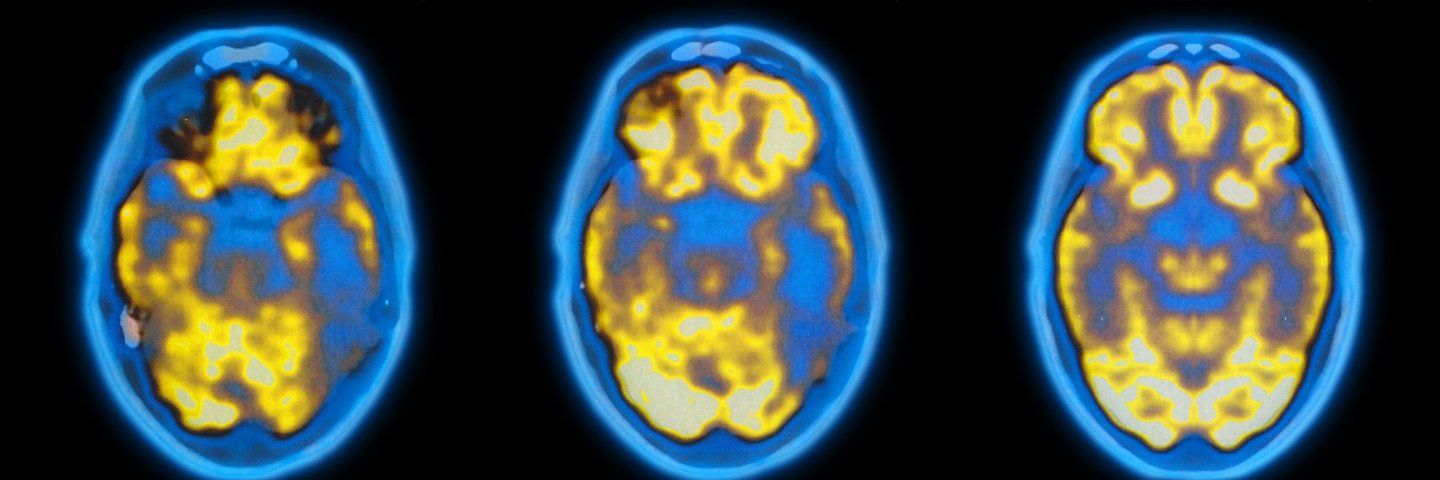

PET scan of a brain